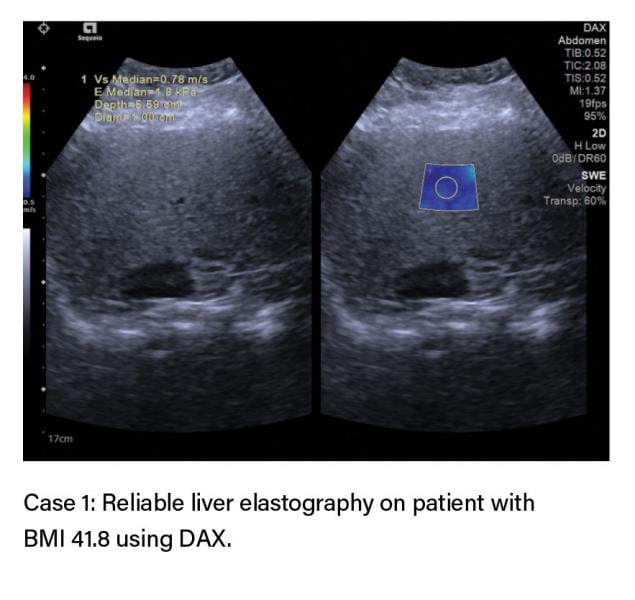

Case: 61 yo with BMI of 41.8, generalized abdominal pain

A 61-year-old female with a BMI of 41.8 (extremely obese) presented for an abdominal ultrasound with liver elastography for generalized abdominal pain and a history of non-alcoholic fatty liver disease (NAFLD).

To assess liver stiffness, an abdominal ultrasound with liver elastography was conducted on a conventional ultrasound system at the imaging center. Liver elastography shear waves are known to attenuate quickly; the attenuation increases with increased subcutaneous tissue. This makes obese patients a challenge for liver elastography exams. Most patient-related confounding factors increase the stiffness value; therefore, a normal value of elastography can be accepted as normal, whereas an increased value must be taken in clinical context.

When conducting the liver elastography exam on the conventional ultrasound system, there were some challenges in acquiring the elastography values due to drop out and limited areas of good quality in the acquisition. The shear wave values that were obtained were extremely elevated and consistent with that of a cirrhotic patient with a median stiffness of 2.05 m/s (13.05 kPa). The patient’s previous lab work and clinical history presented with a normal but fatty liver. For this patient, Dr. Barr brought in the ACUSON Sequoia with DAX to correlate the liver elastography results. Using the DAX, the values obtained were a median stiffness of 0.88 (2.35 kPa) indicating no clinically significant liver stiffness. The liver elastography results on the ACUSON Sequoia with DAX were consistent with the patient’s labs and other clinical considerations. For confirmation, a FibroSure blood test was performed, which came back as normal, confirming the data acquired with the DAX.

“Obesity is a patient factor known as a source of variability in liver elastography exams on conventional technology,” said Dr. Barr. “The pulse generating the shear wave attenuates as it traverses the patient and reaches a point where adequate shear waves are not generated for accurate measurements on conventional technology. What we experienced on this patient was that the ACUSON Sequoia with DAX was able to provide quick, accurate, and reliable elastography measurements even in an extremely obese patient. Now she can continue her routine yearly follow-up for NAFLD.”